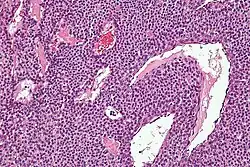

Micrograph of a glomus tumor. H&E stain. | |

Histologically, glomus tumors are made up of an afferent arteriole, anastomotic vessel, and collecting venule. Glomus tumors are modified smooth muscle cells that control the thermoregulatory function of dermal glomus bodies. As stated above, these lesions should not be confused with paragangliomas, which were formerly also called glomus tumors in now-antiquated clinical usage. Paragangliomas do not arise from glomus cells, but glomus tumors do.

By histopathology, glomus tumors can be termed as follows:[8]

- Solid glomus tumor (75% of cases): Consisting predominantly of glomus cells, with poor vasculature and rare smooth muscle cells.

- Glomangioma (20% of cases): Tumors with a prominent vascular component.

- Glomangiomyoma (5% of cases): Tumors with prominent vascular and smooth muscle components.